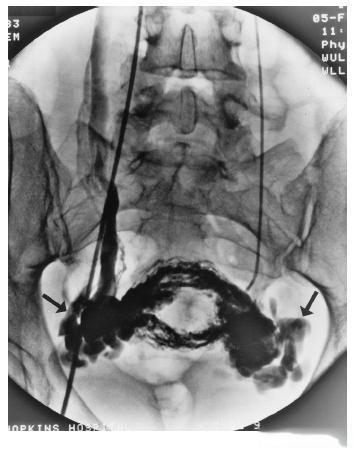

面对这个陌生的疾病,小王最关心的是如何治疗。医生告诉她,轻度PCS可以通过非甾体抗炎药(NSAIDs)和改善生活习惯来缓解症状。但对于症状严重的患者,可以考虑介入栓塞治疗。

介入栓塞治疗是一种微创手术,通过导管将栓塞材料注入到扩张的静脉中,阻断血液流向曲张的静脉。 这种方法可以有效缓解疼痛,提高生活质量。但同时,医生也提醒小王,任何手术都有一定的风险,需要慎重考虑。